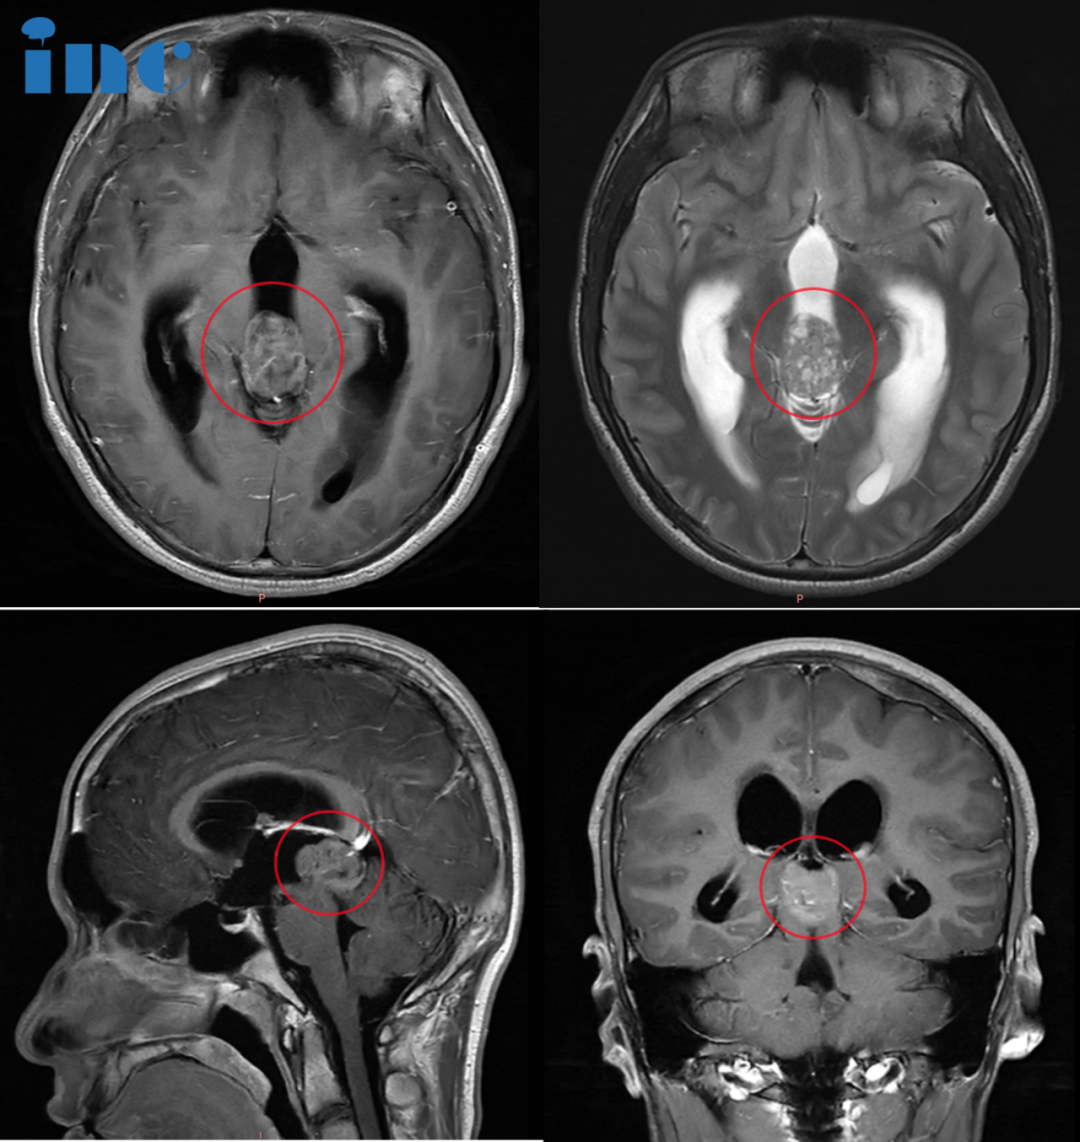

林林在10岁时被诊断出松果体区钙化病变。由于病变位置特殊且体积较小,接诊医生均建议采取保守观察方案。钙化表现通常意味着肿瘤生长缓慢,这让林林全家稍感安心,期待通过保守治疗实现与肿瘤的长期共存。

然而六年后病情发展超出预期。肿瘤出现明显增大并引发梗阻性脑积水,林林的临床症状在这几年间急剧加重,出现眼部胀痛、视力模糊、耳鸣等神经系统症状。日益加重的病情使全家陷入深深不安,曾经的期待转化为现实的失望。

在家人支持下,林林在九天内顺利完成手术。巴教授采用幕下小脑上入路成功切除肿瘤,术后病理证实为生殖细胞瘤。"该类肿瘤实现全切后配合辅助治疗,预后良好,特别是对年轻患者,术后生活无需过多限制。"巴教授的术后随访意见让全家重拾信心。